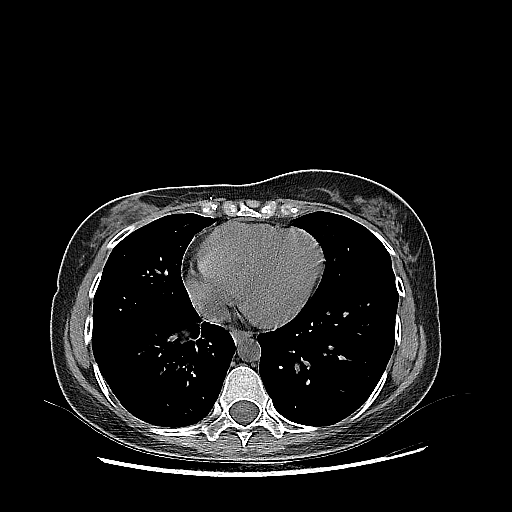

Targeted Slice 70 - Mediastinum Window Analysis (Generated vs Real Venous)

0.784

Mediastinum SSIM

43.0

Mediastinum RMSE

13.8

Mediastinum MAE

Average Mediastinum Window Metrics Across All Slices (103 slices) - Generated vs Real Venous

0.762

Mediastinum SSIM (Avg)

44.5

Mediastinum RMSE (Avg)

15.0

Mediastinum MAE (Avg)

Original NATIVE CT scan (input)

Mediastinum window (WL 40, WW 400 β†’ Low βˆ’160, High +240)